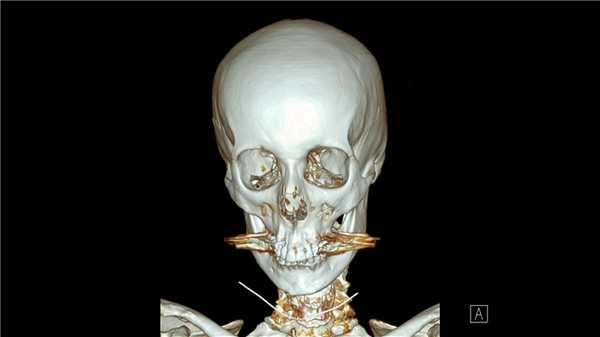

Неизгладимое обезображивание лица вследствие переломов костей лицевого черепа / Морозов Ю.Е., Плотников В.С., Никитин С.А. // Избранные вопросы судебно-медицинской экспертизы. — Хабаровск, 2019. — №18. — С. 149-153.